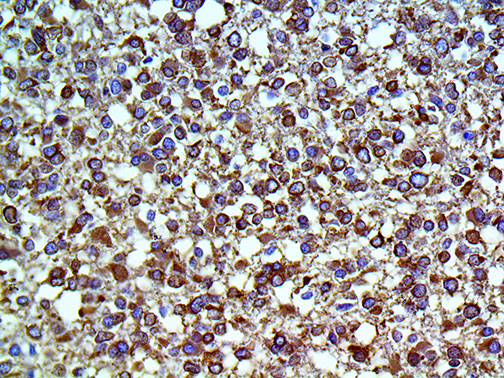

Tau – MMab

Tau is a mouse monoclonal antibody derived from cell culture supernatant that is concentrated, dialyzed, filter sterilized and diluted in buffer pH 7.5, containing BSA and sodium azide as a preservative.